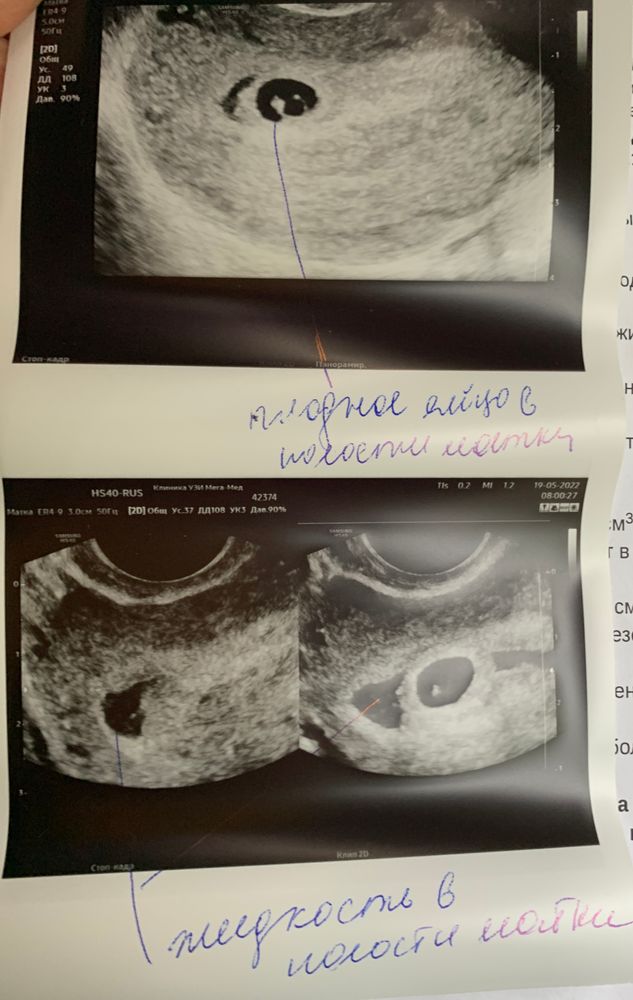

Анастасия , прилагаю фото УЗИ от 19.05. На УЗИ 27.05 и 28.05 не увидели уже это содержимое (предположительно это и была гематома). Сказали, если и было что-то, то рассосалось. Изображение

Мария, да похоже на гематому , видимо вся вышла